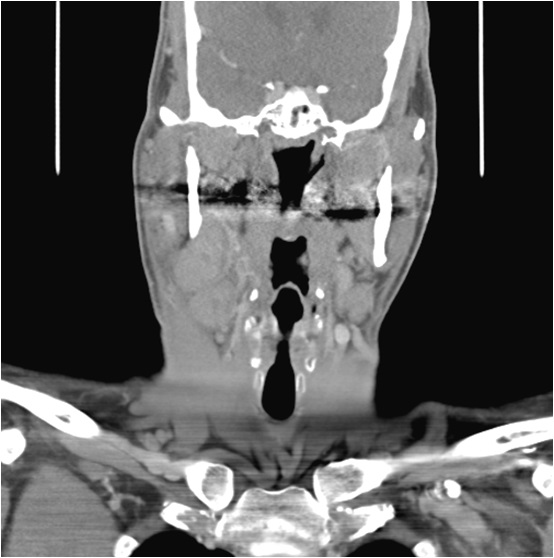

Case Presentation: A 44 year-old African-American man presented to his primary care physician with a five day history of neck swelling and pain associated with chills, night sweats and weight loss. Three days prior to presentation, he was evaluated at a nearby emergency department and prescribed amoxicillin-clavulanic acid without improvement. Physical and laboratory examinations were normal except for four round, tender, right-sided cervical mobile masses. Computed tomography(CT) of the neck with intravenous contrast revealed bilateral, right greater than left cervical adenopathy consistent with possible lymphoma. Flexible fiberoptic laryngoscopy was normal and a fine needle aspiration was inconclusive. He completed a second course of antibiotics with trimethroprim-sulfamethoxazole, again without improvement. Given concern for malignancy, a positron emission tomography(PET) scan was performed and revealed fluorodeoxyglucose uptake in bilateral cervical, axillary and external iliac nodes. As a result, he underwent excisional lymph node biopsy and pathology was consistent with reactive lymphadenopathy without evidence of malignancy. He subsequently underwent an infectious workup which was negative. During his extensive workup, patient developed symptomatic anemia, acute kidney injury and a decrease in his serum albumin. Given his negative malignancy and infectious workup, autoimmune disease was considered. Further staining of the biopsy samples was performed, specifically for IgG4 and HHV-8. HHV-8 staining was negative, however there were greater than 50% IgG4 cells in the sample. Laboratory examination was also notable for an elevated serum IgG4 level. A diagnosis of IgG4-related disease was made and he was initiated on steroids, a mainstay in the treatment of this condition. On a subsequent visit, his symptoms had improved, but unfortunately, patient was lost to follow up.